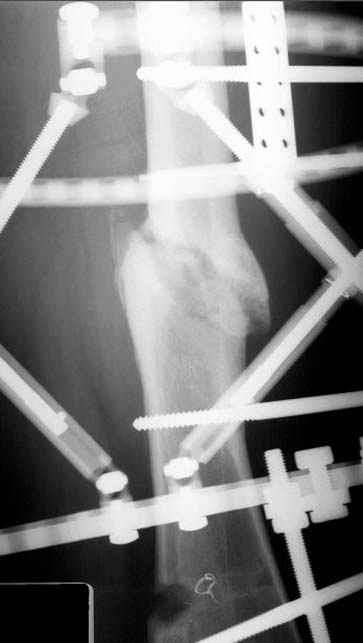

5:24 Рентгенограмма таза, вызывают врача ортопеда (снимок N1), его диагноз: закрытый переломо-вывих правого тазабедренного сустава, получает добро на закрытую репозицию в приемном отделении

5:38 Дважды неудачная попытка закрытой репозиции в приемном отделении

N 2

6:20 ответстенный врач принимает решение о репозиции в условиях операционной, предупреждаются родственники и больной, что при неудачной закрытой репозиции, о возможности открытой репозиции и фиксации задней стенки вертлужной впадины.

7:30 начало операции, больной на спине, попытка репозиции после анестезии N3, укладка больного на боку, доступ Kocher- Langenbeck, состояние седалищнего нерва около 2.5см кровоподтек, через joistick головка бедра приподнята, освобовождение сустава, фрагмент заднего края более 3х4 см репонирован на свое место. После промывания

сустава, репозиция вывиха (N4), фиксация фрагмента 2.7(4) мм шурупами и допольнительно реконструктивной пластиной на 8 дырок, фиксация 3.5мм шурупами проксимально и дистально.

Интраоперционные N5 косая запирательная и N6 подвздошный снимок